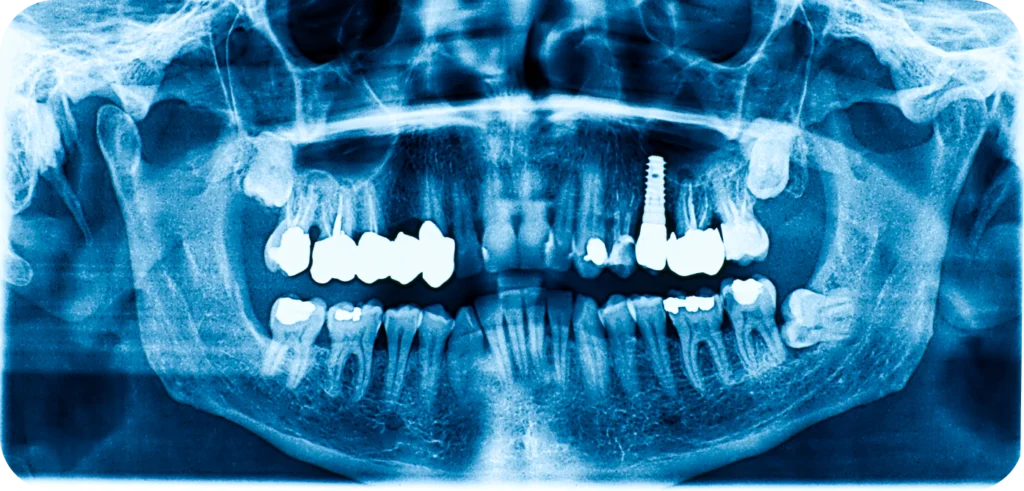

Avant de poser un implant, le praticien effectue un examen clinique et radiologique. Il mesure la profondeur des poches parodontales. Il observe la stabilité des dents voisines et évalue la qualité de l’os. En complément, une radio panoramique ou un scanner 3D peut révéler des foyers invisibles à l’œil nu.